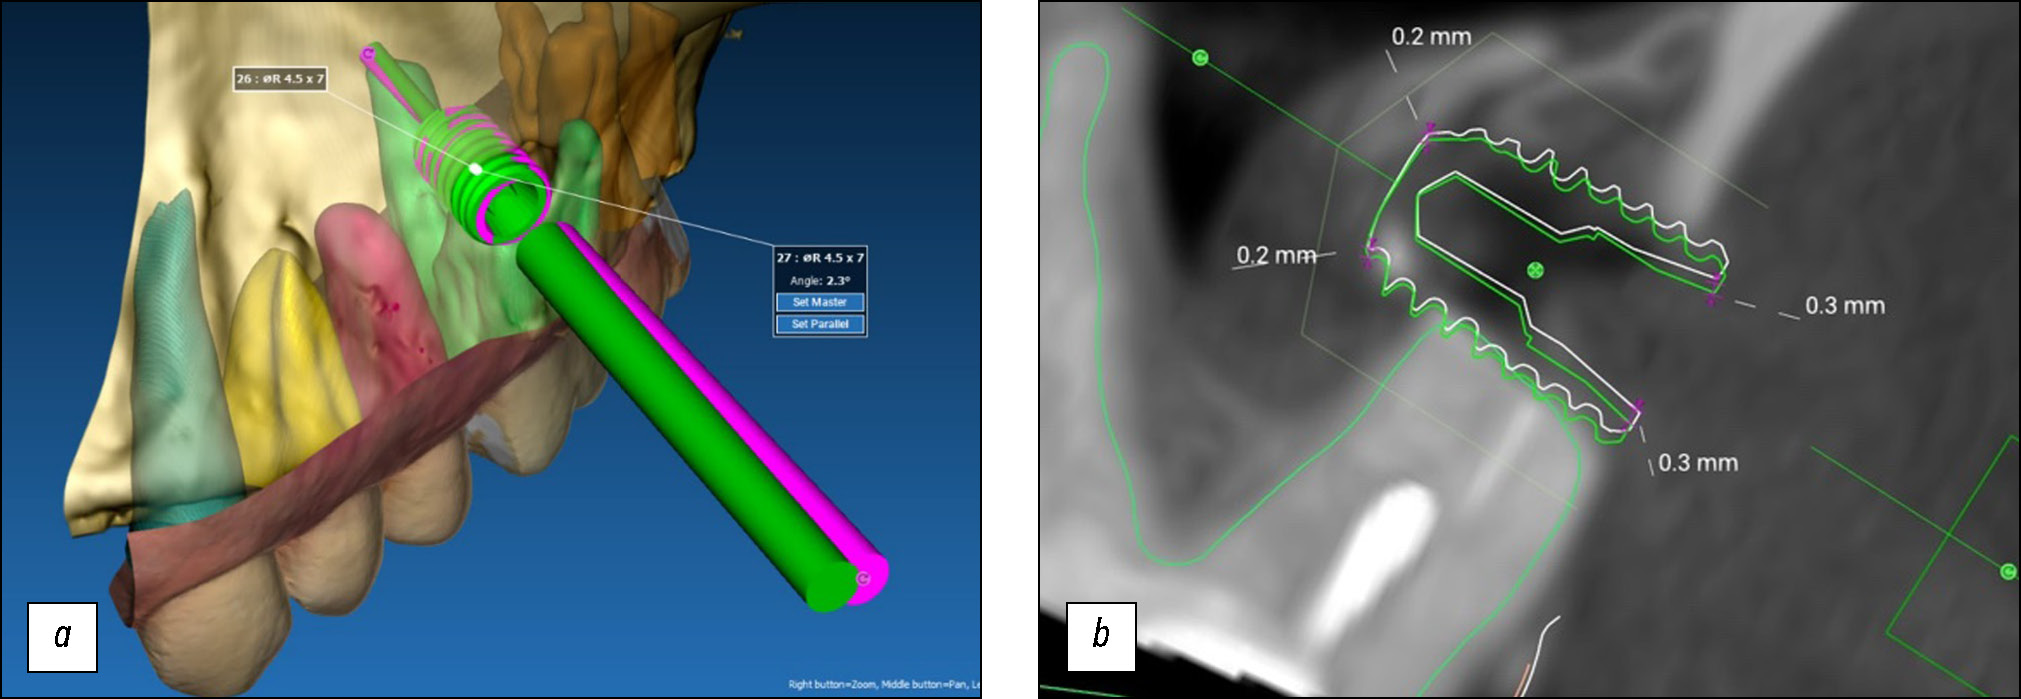

- Цифровое планирование хирургического доступа к зоне вмешательства. После сегментации зоны вмешательства хирург выбирал оптимальное местоположение хирургического доступа. Для этого использовали программу RealGuide 5.3, предназначенную для проведения операций по имплантации под визуализационным контролем. Однако вместо виртуальной установки зубного имплантата в требуемом положении виртуально помещали цилиндр, размер которого соответствовал внутреннему размеру трепанационного бора. Цилиндрический имплантат диаметром 5 мм виртуально устанавливали в месте планируемого хирургического доступа (рис. 14). В формате STL создавали и сохраняли виртуальный шаблон для сверления, обеспечивающий ориентацию трепанационного бора, наружный диаметр которого соответствовал цилиндрическому имплантату.

Рис. 14. Этап планирования хирургического доступа.

В программе RealGuide 5.3 для оценки точности навигационной системы было проведено сравнение результатов компьютерной томографии пациента до и после вмешательства (DICOM-файлы). В сформированное отверстие в кости устанавливали новый цилиндрический зубной имплантат диаметром 5 мм. Положение имплантата после вмешательства сравнивали с заданными положением. В программе вычисляли расхождение между заданным и фактическим хирургическим доступом.

Результаты проверки точности работы навигационной системы. Среднее угловое отклонение (в градусах) хирургического доступа после применения системы AR-навигации составило 2,5°. При проведении хирургического вмешательства в области боковых зубов угловое отклонение было несколько выше (рис. 17).

Рис. 17. Угловое отклонение между заданным и фактическим хирургическим доступом: a — трёхмерная визуализация смещения, где зелёным отмечен достигнутый хирургический доступ, розовым — запланированный; b — фронтальный срез, запланированный хирургический доступ (отмечено белым), достигнутый (отмечено зелёным).